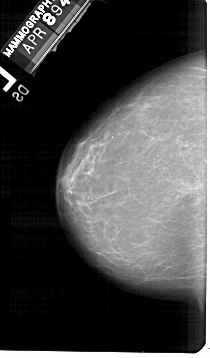

A_1548_1.RIGHT_MLO

A_1548_1.RIGHT_CC